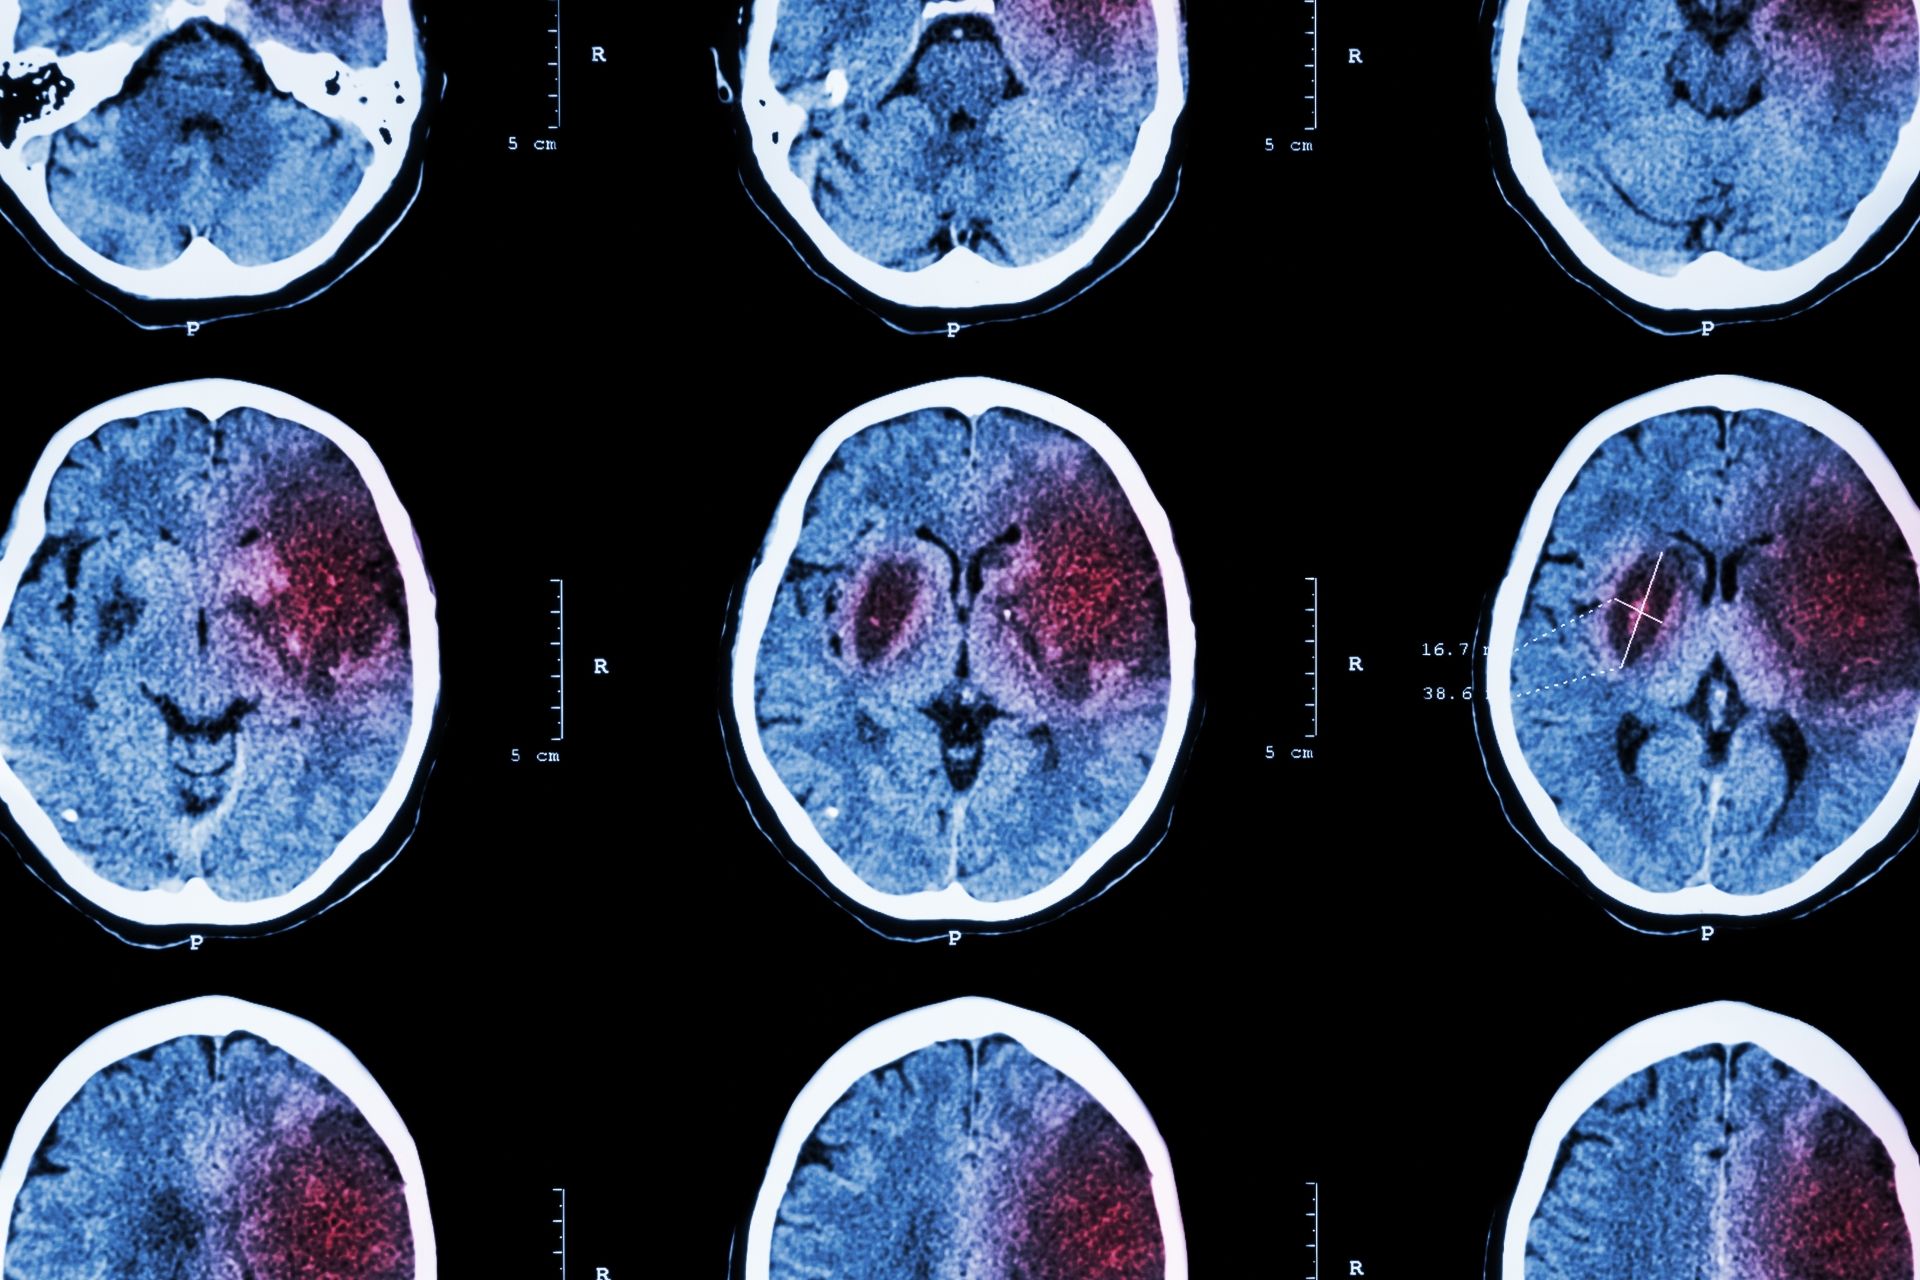

Aivoinfarktiin sairastuneet alttiita myös veritulpille

Aivoinfarktipotilaat ovat huomattavan suuressa vaarassa sairastua laskimoveritulppiin infarktia seuraavien kuukausien aikana. Tämän jälkeen riskit kuitenkin nopeasti pienenevät, tuore tutkimus osoittaa.